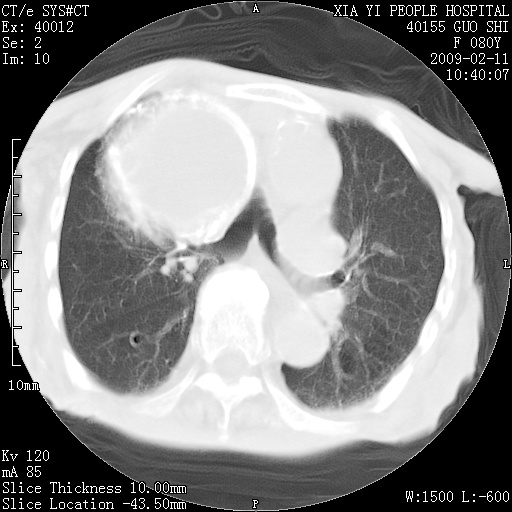

以下是引用随光逐影在2009-2-16 16:34:00的发言:[br]1)考虑右前纵隔皮样囊肿。2)双侧少量胸腔积液。

以下是引用zjzjr在2009-2-16 17:30:00的发言:[br]支持囊性畸胎瘤 双侧少量胸腔积液。